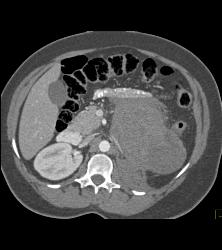

GIST Tumor